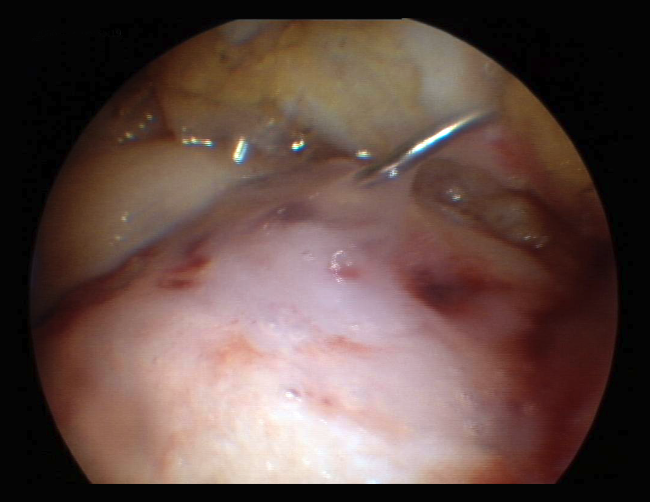

Despite these undeniable and proven benefits, however, chitosan is very unstable, and the elaboration of products containing it therefore poses major challenges. A very interesting property of this biopolymer is the fact that when in liquid state, it transforms into a semisolid gel upon reaching human body temperature(24). This discovery was very useful in searching for a formulation that may be injected into a joint such as the knee in the course of an arthroscopic procedure, with solidification in situ in only a few minutes. The decision was therefore made to use it as a coadjuvant in BMS procedures. In 2005, the Canadian company BioSyntech – posteriorly Piramal Healthcare (Canada), Bio-Orthopedics Division – started an international, randomized, comparative clinical study contrasting microfractures alone with microfracture plus versus their product, BST-CarGel® (currently Smith & Nephew, Wartford, UK). The results after both 12 months and at 5 years of follow-up evidenced sustained superiority over time of BST-CarGel® versus microfractures alone. This superiority was reflected by both the greater hyaline quality and quantity of the formed tissue, as measured objectively using quantitative magnetic resonance imaging (MRI) techniques(25,26) (Figure 4).

Figure 4. A: extensive chondral lesion of the internal condyle covered by the clot after augmented microfractures with chitosan based hydrogel; B: arthroscopic appearance of the totally covered zone and biopsy sampling orifice after 13 months; C: histological appearance of the biopsied zone. Note the "hyaline" appearance of the tissue and good interdigitation with the subchondral bone. Image of the randomized study with BST-CarGel.